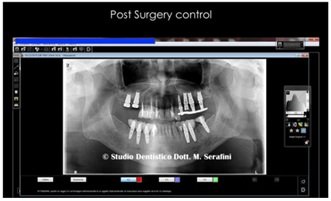

At this point it was decided to extract all the posteriors teeth and to perform two large lifts of the maxillary sinuses, 6 months apart from each other, because in the meantime we were interested in the lower arch, which is also strongly compromised by periodontopathy (Figures 25,26).

Figure 25: Post surgery Control Left Side.

Figure 26: Post Surgery Control Right Side and Lower Implants.